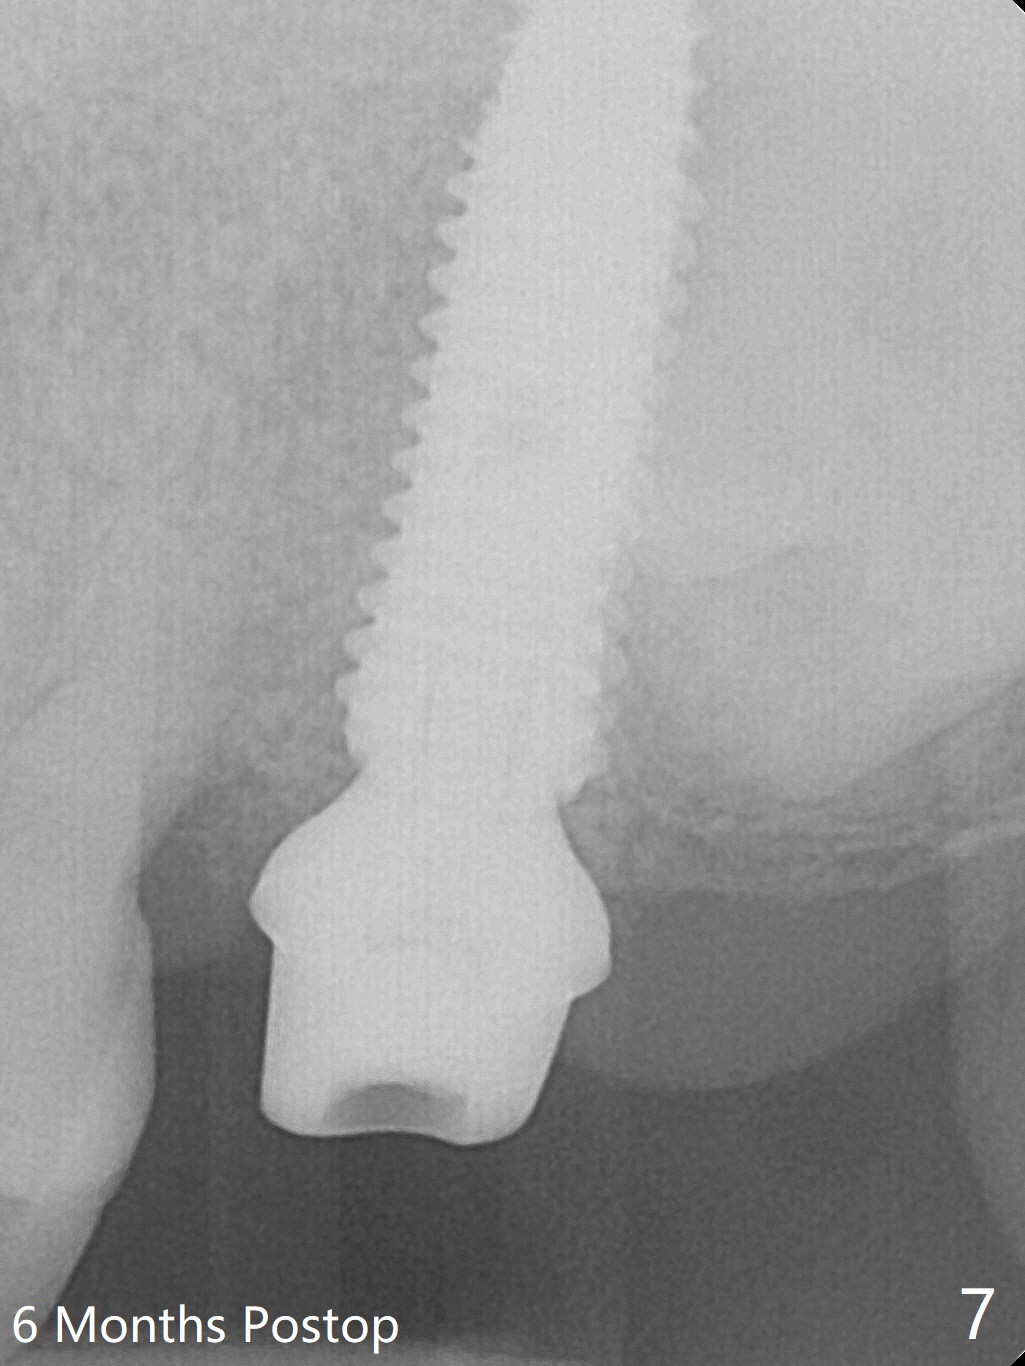

Extraction of the tooth #15 with short clinical crown (suggesting bruxism, Fig.1) reveals a vertical root fracture (Fig.2 <). It seems unnecessary and difficult to create osteotomy in the mesial slope. What can be done is to place starter and 2 mm drills as mesial as possible (Fig.3 (red dashed line: sinus floor). After use of Lindamann bur to move the osteotomy mesially and sequential osteotomy until 3.8x18 mm, a 4.5 mm tap is inserted with clearance from the impacted tooth #16 (Fig.4). A 5x15 mm implant is placed with >60 Ncm with clearance from the 3rd molar (Fig.5,6). If the impacted tooth were removed, the primary stability is expected to be reduced. Impression is taken 6 months postop with 19/20 implants (Fig.7). The bone graft remains in the crestal area immediately and 11 months post cementation (Fig.8,9 *). In the other word, new crestal bone forms after extraction.